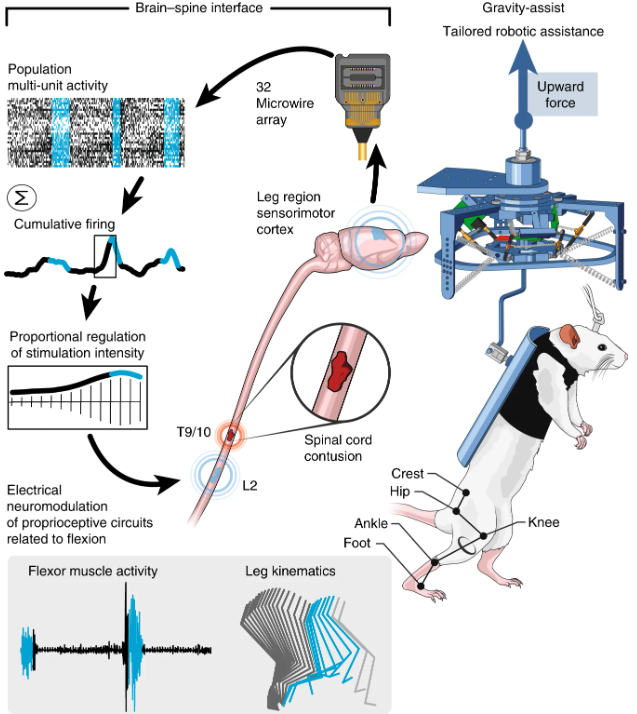

قطع نخاع زمانی رخ میدهد که نخاع در اثر آسیب شدید بهطور کامل یا جزئی دچار گسستگی شود و ارتباط میان مغز و بخشهای پایینی بدن قطع شود. این آسیب میتواند منجر به از دست رفتن توانایی حرکت، حسی، و کنترل اندامها شود. اخیراً، تکنولوژیهای پیشرفته مانند "پل نخاعی" بهعنوان روشی جدید برای بازگرداندن عملکرد عصبی در افراد دچار قطع نخاع مطرح شدهاند. این فناوری شامل اتصال به دو بخش سالم و آسیبدیده نخاع متصل میباشد که از طریق الکترودهای کوچک، سیگنالهای الکتریکی را از بخش سالم نخاع دریافت میکند و سپس این سیگنالها را بهصورت مستقیم یا با پردازش و تقویت، به بخش آسیبدیده منتقل میکند. به این ترتیب، مسیر عصبی که بهواسطه آسیب قطع شده بود، بهطور مصنوعی بازسازی میشود. آزمایشهای اولیه نشان دادهاند که این روش میتواند به بهبود قابل توجهی در بازیابی حرکت و حواس در بیماران کمک کند و به آنها امکان بازگشت به زندگی عادیتر را بدهد. با این حال، این تکنولوژی همچنان در مراحل اولیه توسعه قرار دارد و تحقیقات بیشتری برای بهینهسازی و افزایش اثربخشی آن مورد نیاز است. هم اکنون آزمایشات حیوانی این روش بر روی موش توسط تیم دکتر کورتین در دانشگاه EPFL با موفقیت سپری شده است.